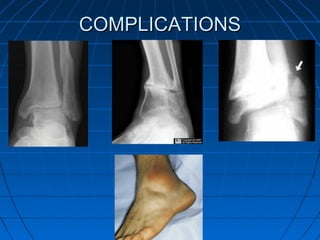

ComplicationsComplications

 PerioperativePerioperative

• MalreductionMalreduction

• Inadequate fixationInadequate fixation

• Intra-articular hardware penetrationIntra-articular hardware penetration

 Early PostoperativeEarly Postoperative

• Wound edge dehiscence/necrosis,Wound edge dehiscence/necrosis,

• Infection,Infection,

 LateLate

• Stiffness,Stiffness,

• Persistent oedema,Persistent oedema,

• Malunion,Malunion,

• Nonunion,Nonunion,

• Post-traumatic arthritis,Post-traumatic arthritis,

• Hardware related complications.Hardware related complications.